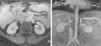

Takayasu's arteritis associated with Crohn's disease